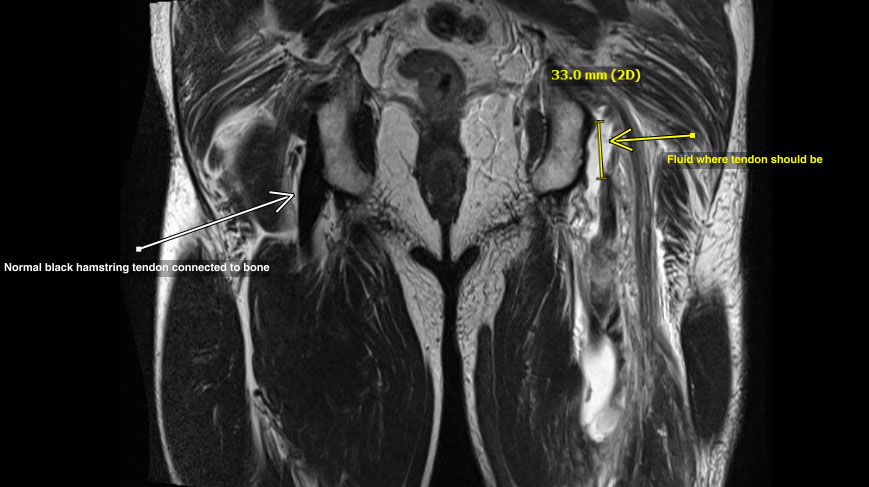

This MRI image is like a “slice” showing both the normal and abnormal buttock, back of the thighs at the bottom of the screen. The two sides should be symmetrical.